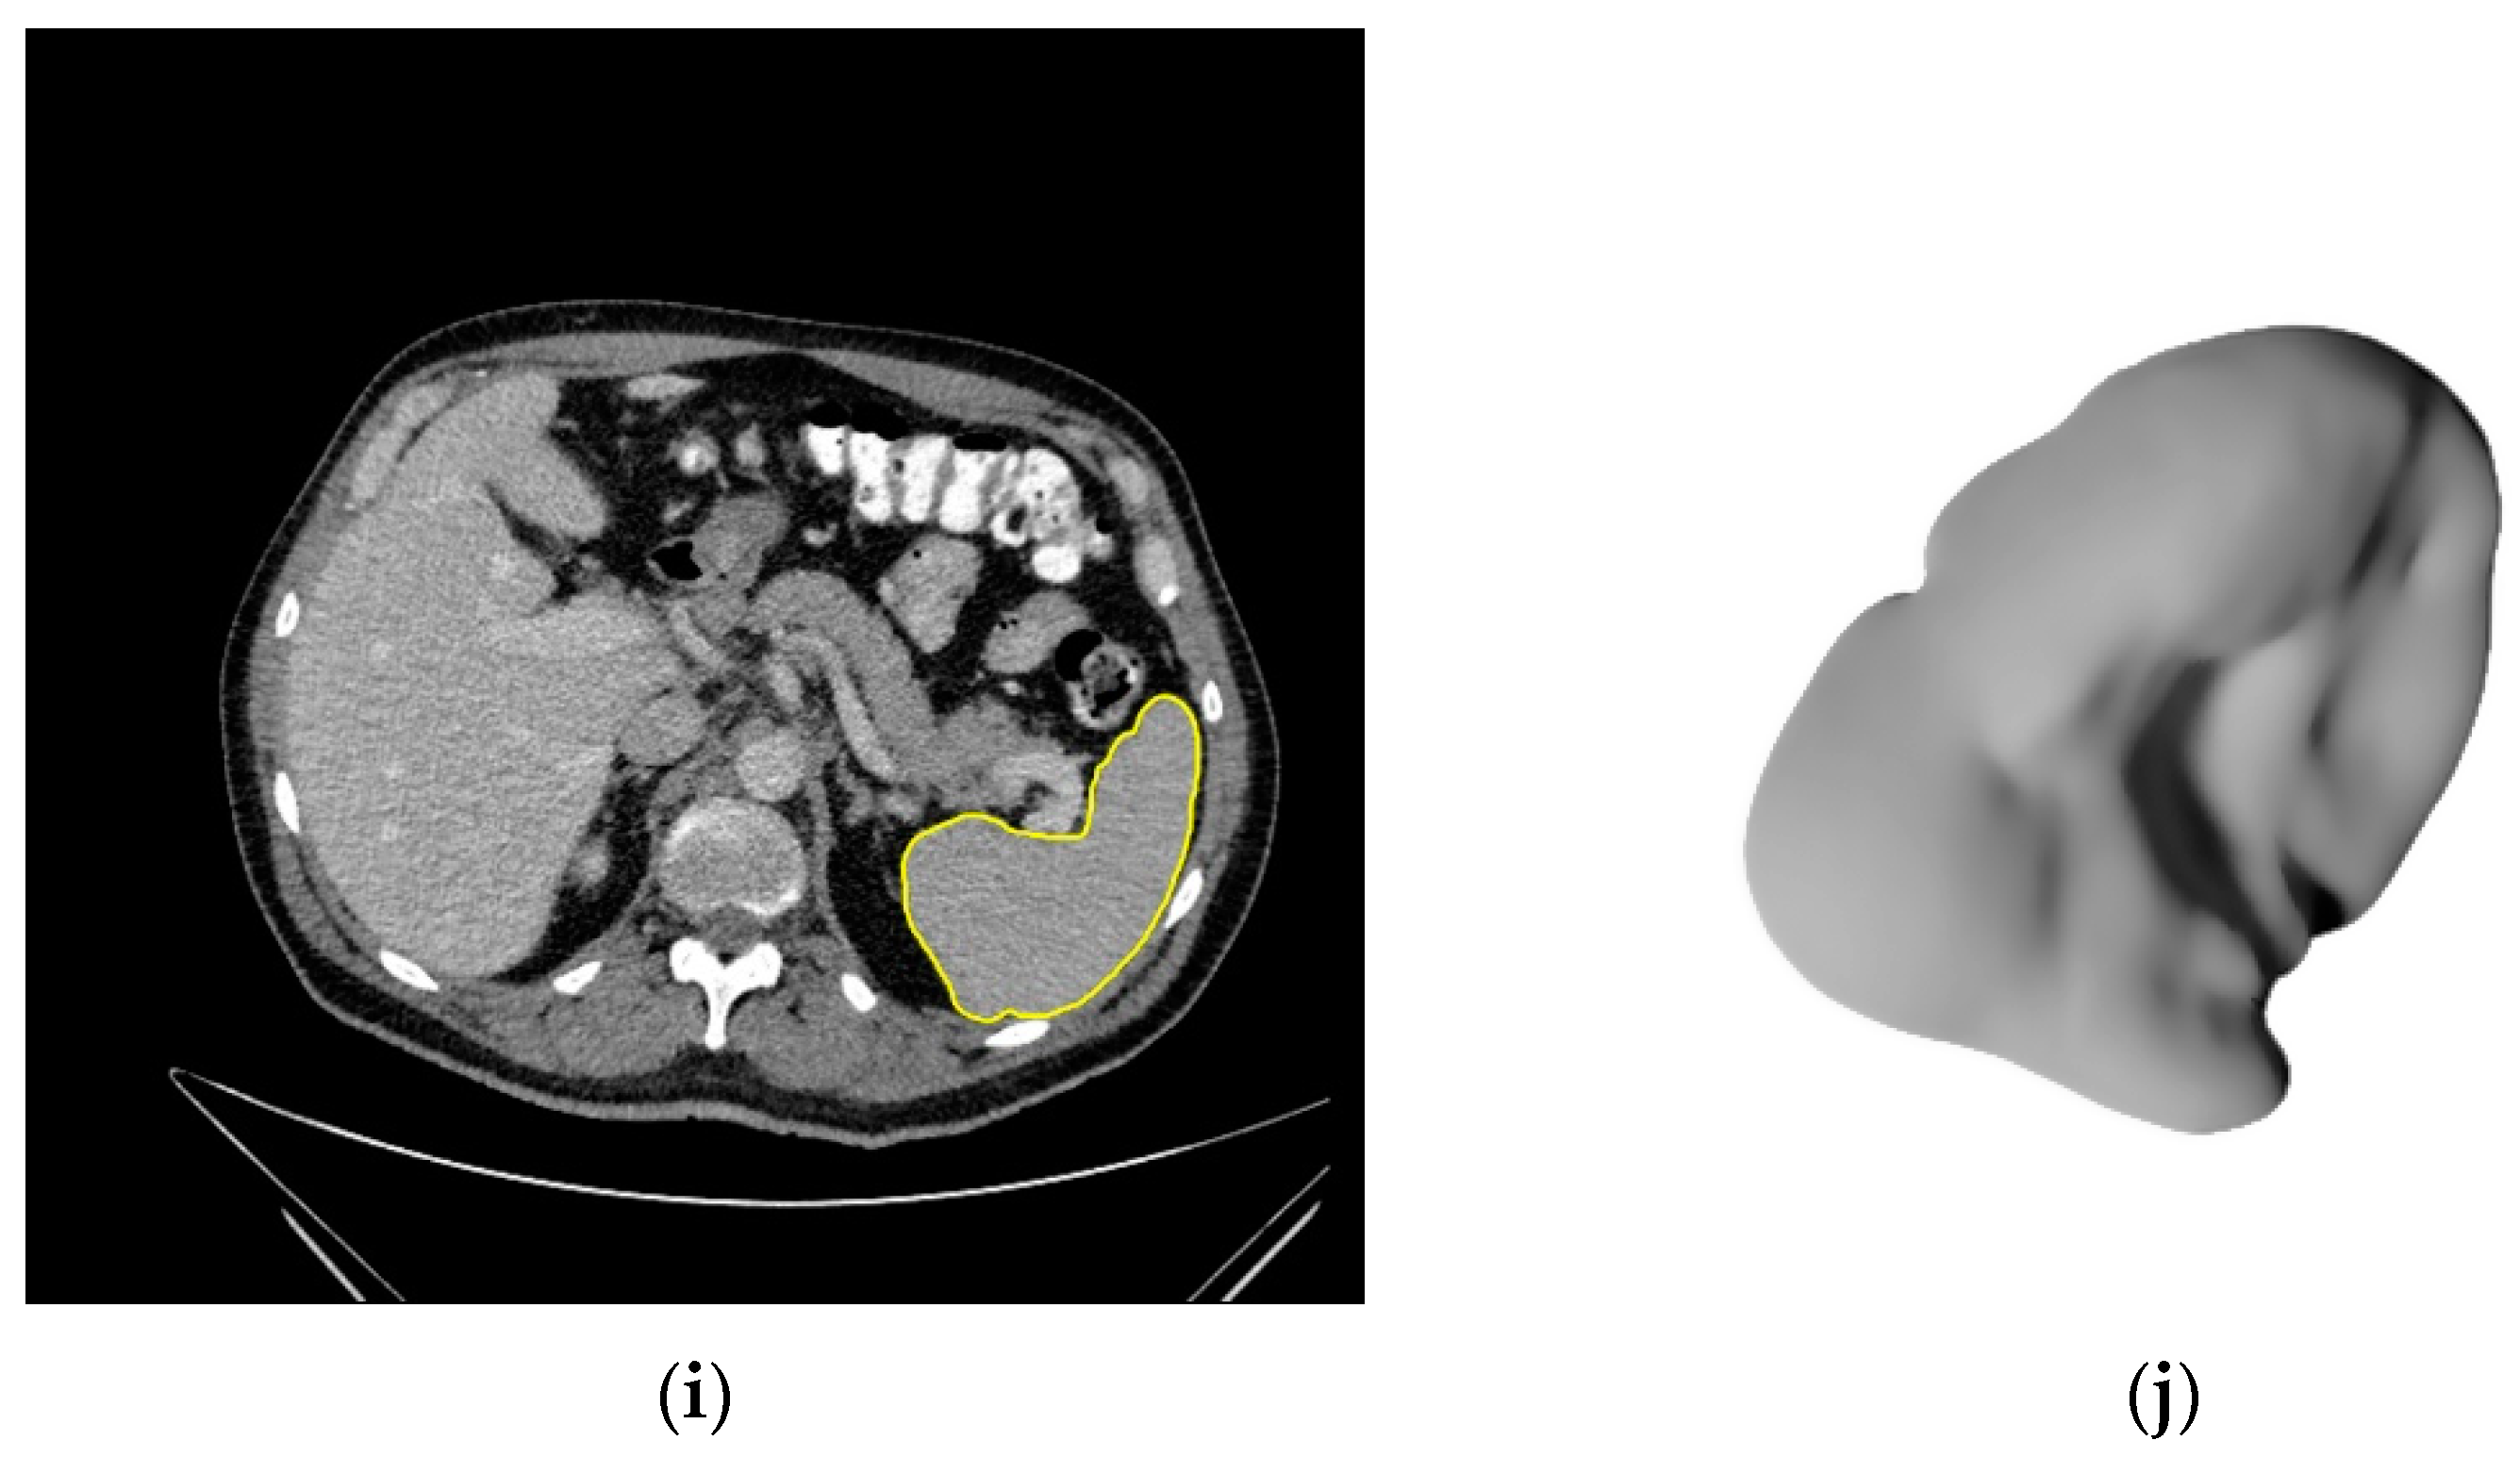

2.3. Image Segmentation

3.2. Segmentations of the Spleen